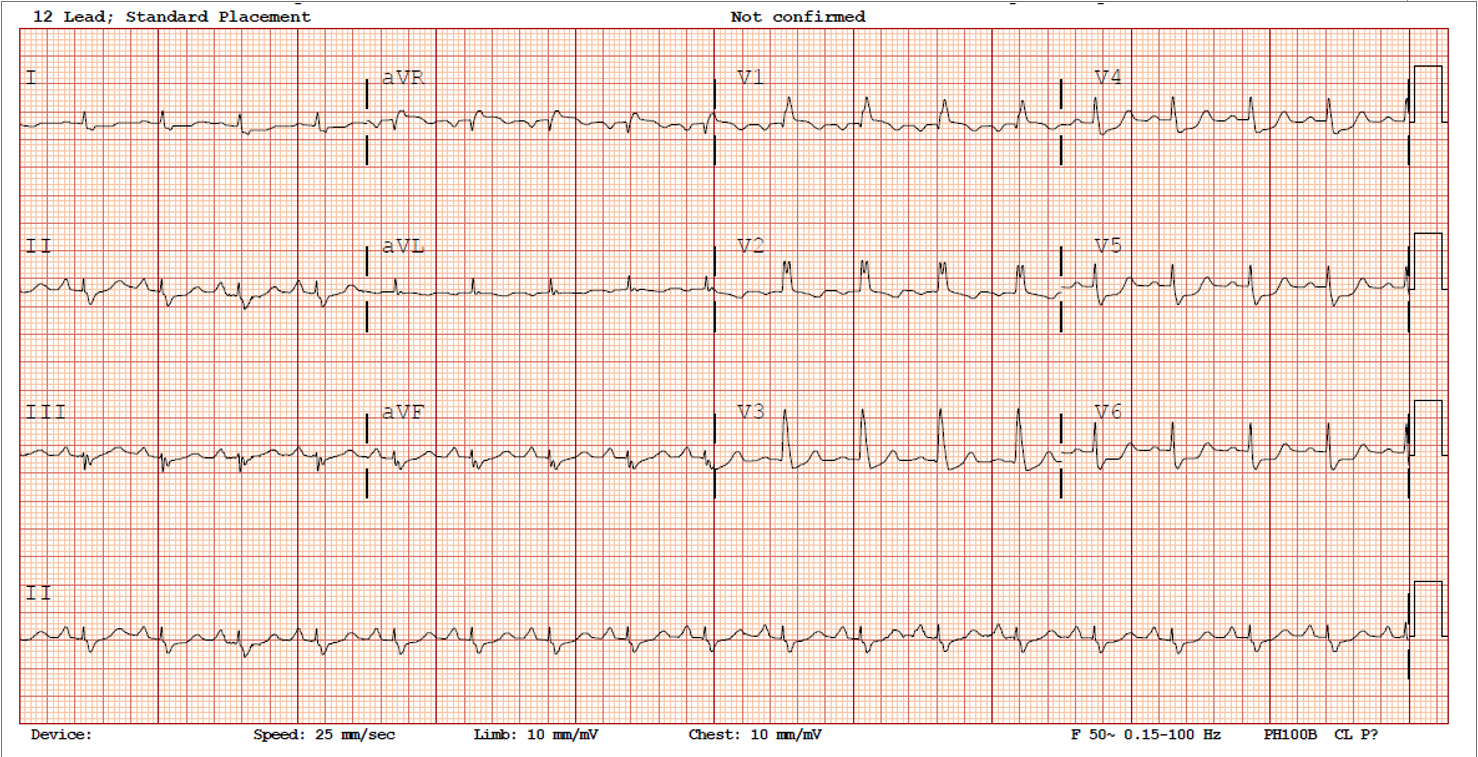

Relevant Test Results Prior to Catheterization

Full blood count, renal function tests were normal. High-sensitivity Troponin I was elevated. Echocardiography showed LVEF 25%.